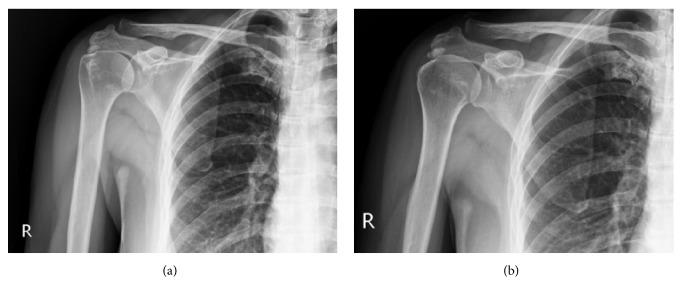

Extracorporeal shock wave therapy (ESWT) had been proved to be beneficial in calcific tendinosis; however, the treatment efficacy in noncalcific tendinosis of rotator cuff still remains controversial. The present study was to compare the outcomes ESWT among the noncalcific rotator cuff tendinosis and different types of calcific tendinosis on the basis of similar shoulder functional status.

A retrospective, comparative study was conducted with the enrollment of 20 patients in each group through propensity score matching in a 1:1:1 ratio from 291 patients who underwent single ESWT for painful shoulder tendinosis. The patients were divided into three groups which included noncalcified tendinosis (NCTS), type I dense calcified tendinosis of shoulder (DCTS), and type II and type III translucent calcified tendinosis of shoulder (TCTS) according to Gartner and Heyer classification. The clinical evaluation included the subjective pain score with visual analog scale (VAS) and functional outcome with Constant and Murley score (CMS).

通过倾向性评分匹配,以 1:1:1 的比例从 291 例接受单次 ESWT 治疗肩部疼痛性肌腱病的患者中,回顾性比较了每组 20 例患者。根据 Gartner 和 Heyer 分类,患者分为三组:非钙化性肌腱病(NCTS)、Ⅰ型肩致密钙化性肌腱病(DCTS)和Ⅱ型和Ⅲ型透明性钙化性肌腱病(TCTS)。临床评估包括视觉模拟量表(VAS)的主观疼痛评分和Constant 和 Murley 评分(CMS)的功能结果。